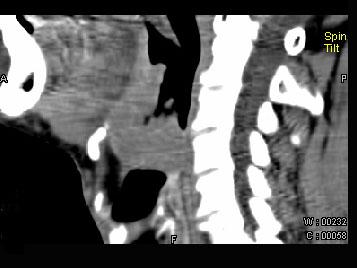

问题 男,74岁,咽喉部不适一年余,近两三个月咽喉疼痛,吞咽困难,CT如图所示,最可能诊断是 ( )

选项 A、声门下区癌 B、跨声门型癌 C、会厌癌 D、声带癌 E、喉癌

答案 C